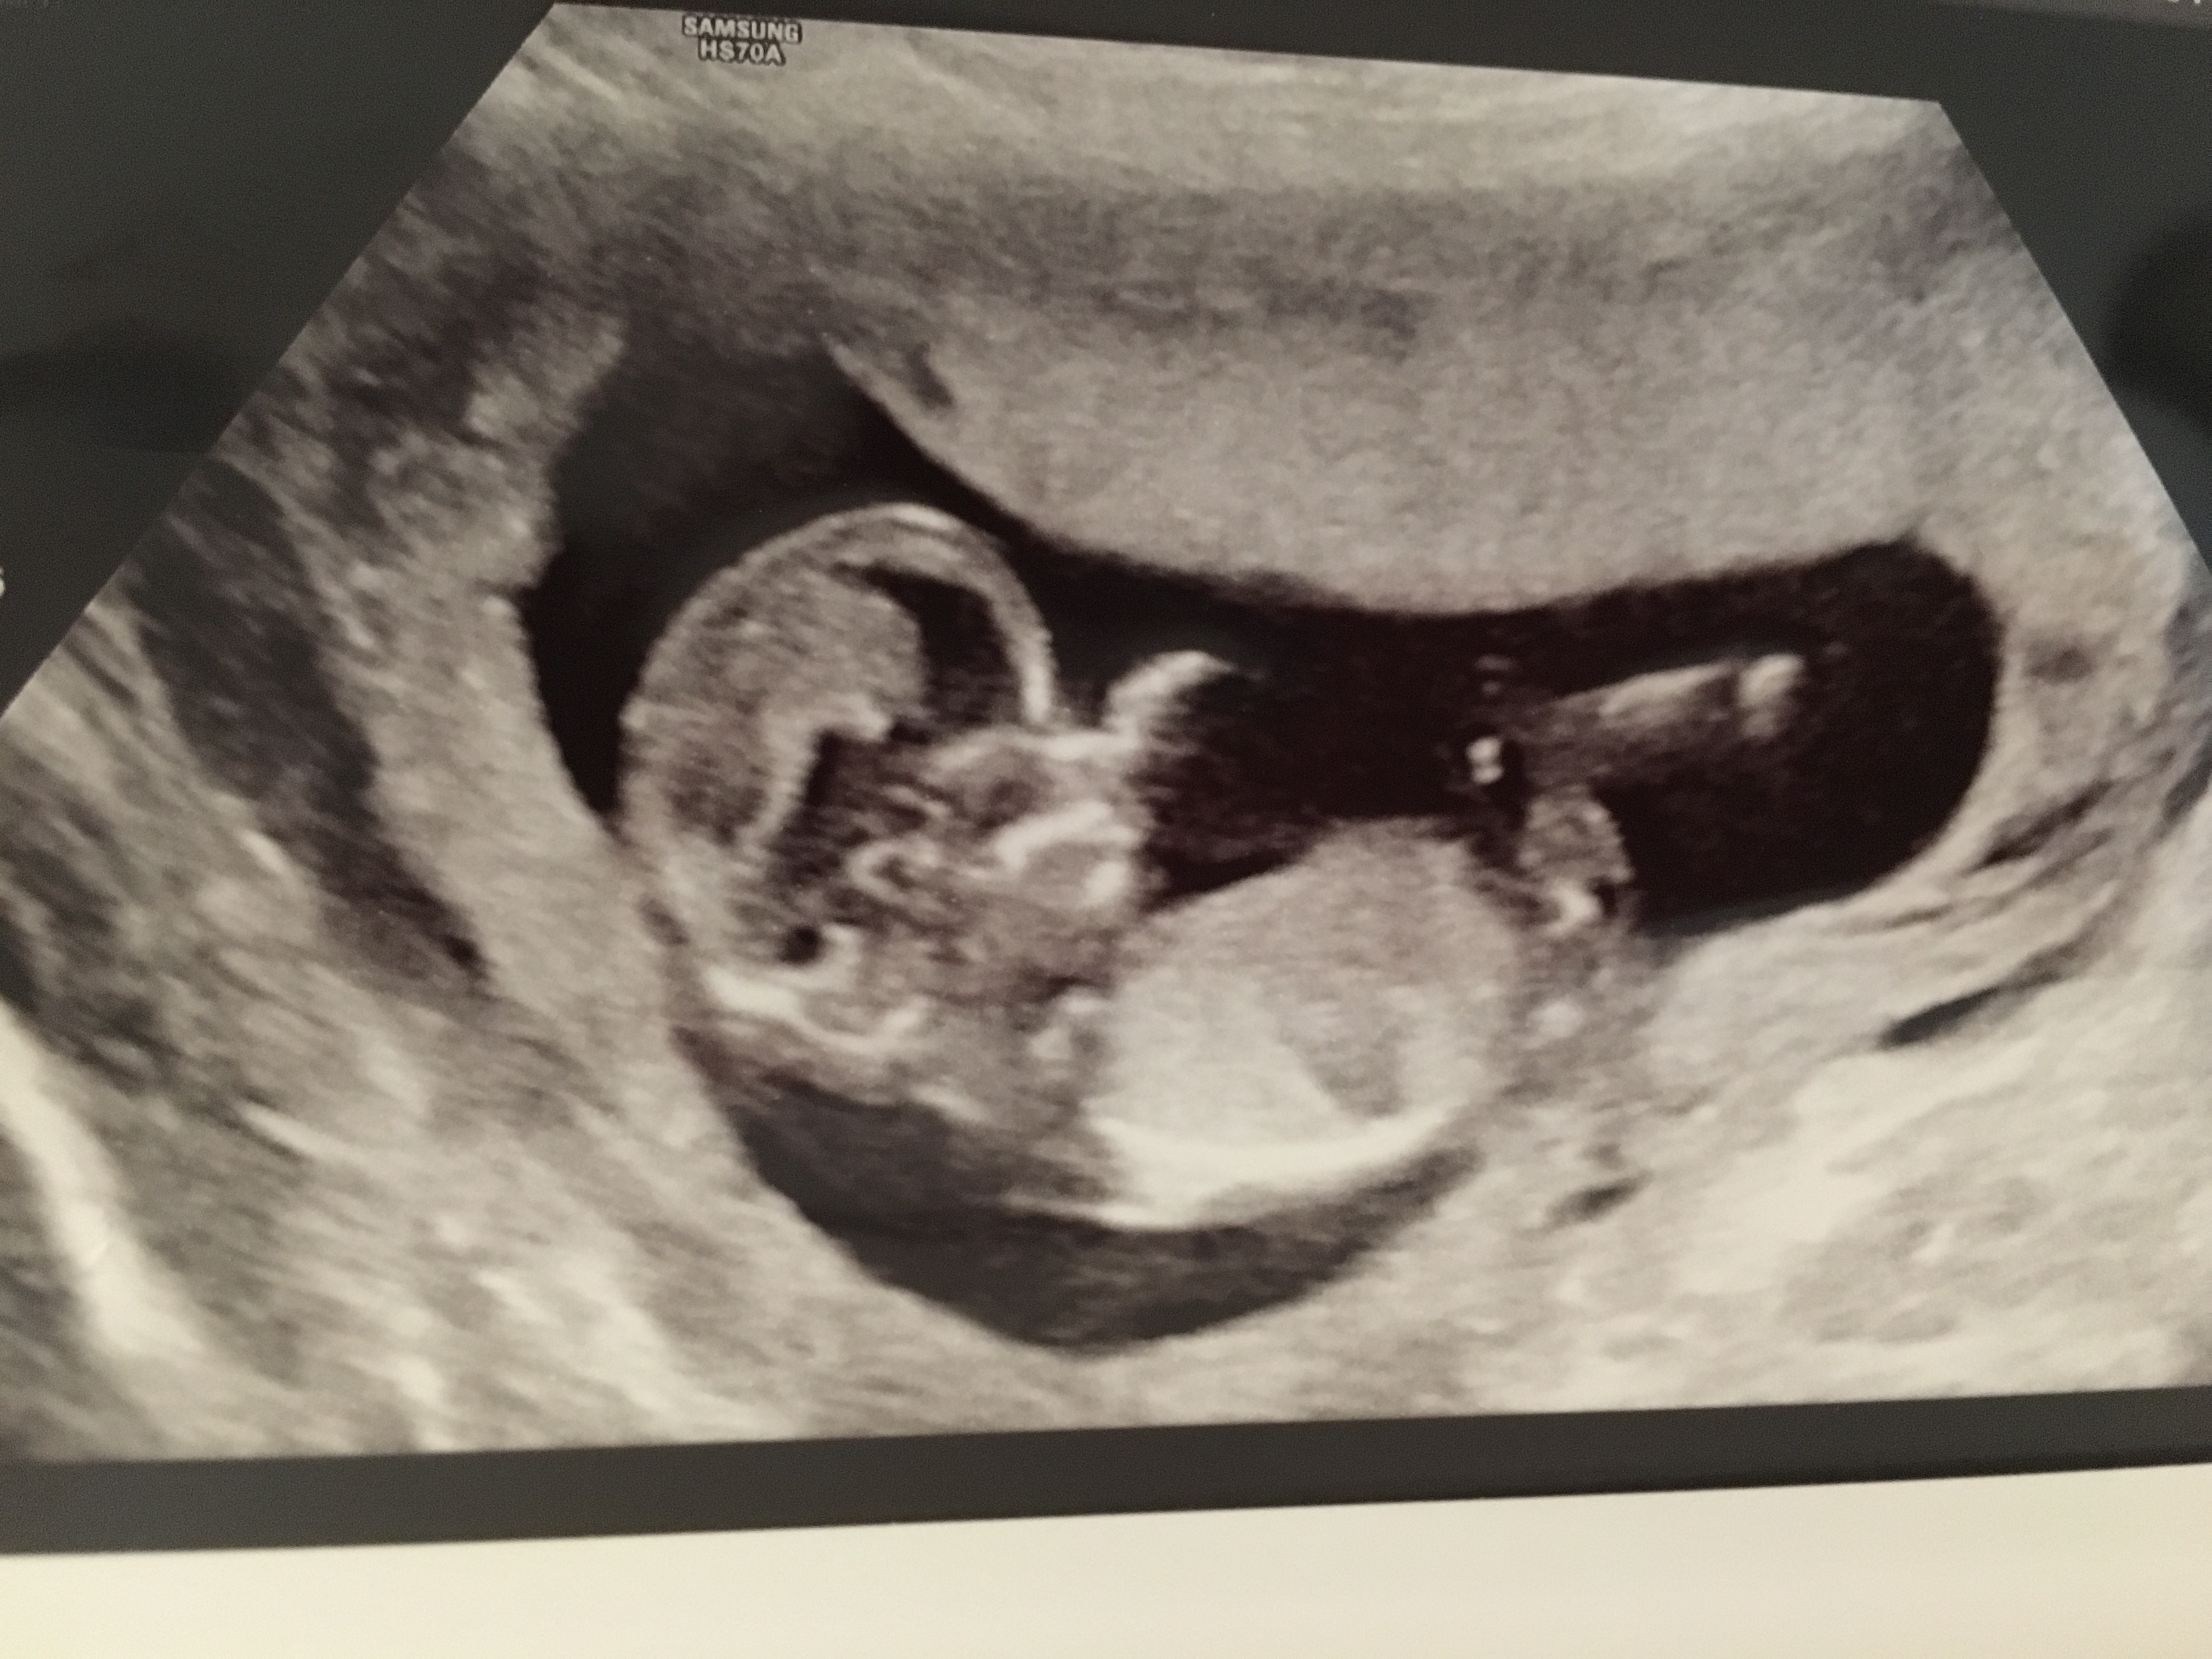

13w nub??

Not 100% sure if this is a nub or not. If it is, it looks boyish to me. All potty shots look clearly girl with 3 lines and no protrusion whatsoever. With my las pregnancy saw a clear penis protrusion at 13 weeks potty shot. Curious to get some feedback :) Attachment 33904Attachment 33905Attachment 33906

The first picture doesn't show a nub I think... looks a girl to me! Congrats

Very boyish :) The potty looks boyish too, boys can have 3 lines as well. I would say 99.9% boy.